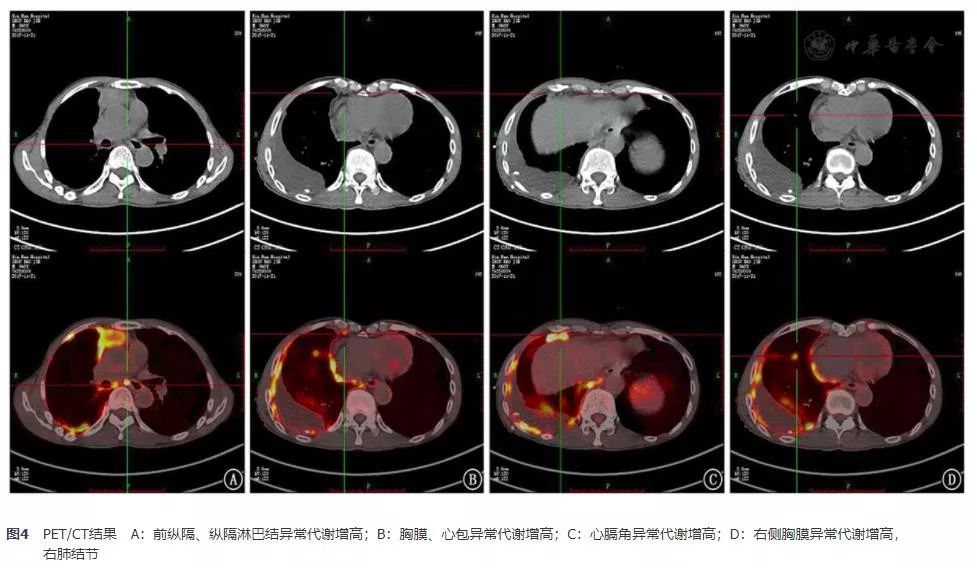

进一步行PET/CT检查,提示:(1)前上纵隔软组织块影伴代谢异常增高,考虑胸腺恶性肿瘤可能,邻近主动脉受累待排;膈区、心膈角、纵隔及右肺门淋巴结转移;右侧胸膜多发转移;右肺内多发小结节影,代谢不高,转移待排。(2)右侧胸腔包裹性积液引流中;右下肺少许炎症。(3)肝多发囊肿;左肾多发高或低密度囊肿。(4)双肾上腺代谢稍高,考虑增生性改变,建议随访。(5)前列腺增生,*丸睾**鞘膜积液。(6)多发椎体异常及含气腔,考虑良性可能大,建议必要时行核磁共振检查(图4)。

图4 PET/CT结果 A:前纵隔、纵隔淋巴结异常代谢增高;B:胸膜、心包异常代谢增高;C:心膈角异常代谢增高;D:右侧胸膜异常代谢增高,右肺结节